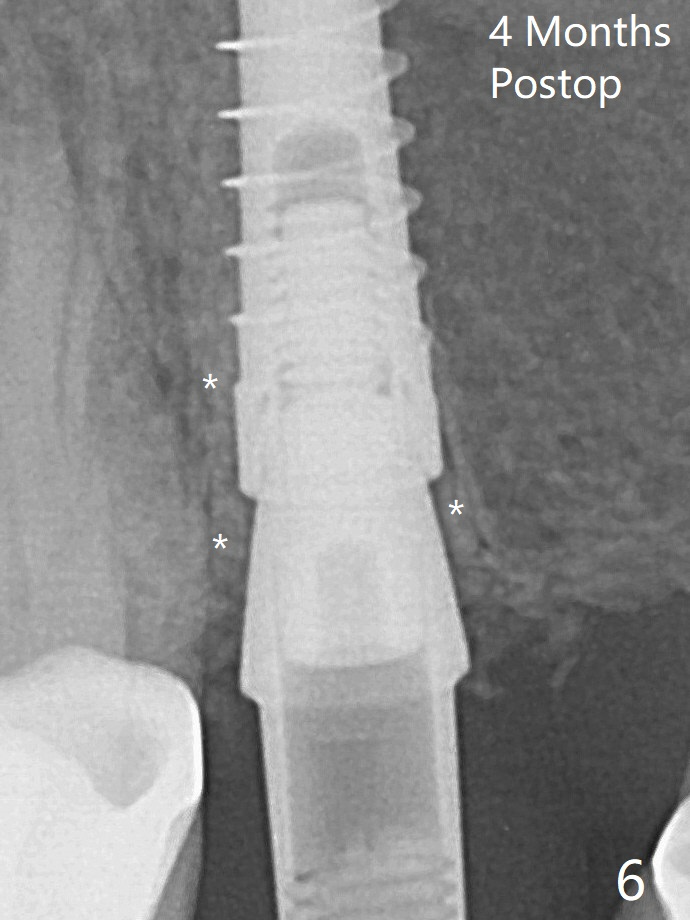

A relatively large 2-piece implant (3.5x13 mm) is placed (Fig.3), but a 4x5.7(2) mm abutment is incompletely seated (<).  Use of 4.6 and 5.6 mm bone profile drills does not appear to solve the problem.  The implant is backed up to the supra-gingival level so that it seems easier physically to insert the same abutment into the implant securely.  Then both of them are torqued into the place together (Fig.4).    The bone graft remains in place 4 months postop (Fig.6).